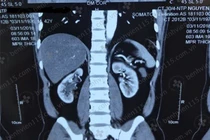

Tá hỏa vì thận ứ nước cứ tưởng đau lưng thông thường

Người đàn ông bị đau lưng âm ỉ suốt 1 năm do thận ứ nước được bác sĩ phẫu thuật bằng phương pháp nội soi tạo hình khúc nối bể thận - niệu quản.